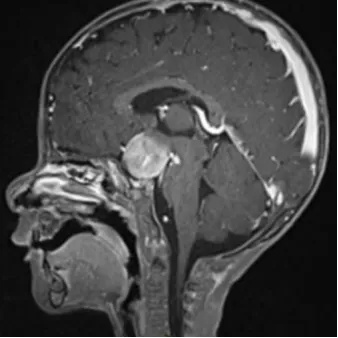

2021年7月中旬,父母向孩子的医生报告了一些眼球活动异常(间歇性水平眼球震颤)和孩子头部的晃动。7月17日,医生立即进行了核磁共振检查,发现了鞍上-下丘脑的肿块。肿瘤的前后径约为2.4厘米,横径为2.7厘米,头尾径为2.3厘米。它在T1加权图像中呈低信号,在T2加权图像中呈高信号,并且在使用造影剂增强后明显强化。

尽管病变已经浸润到了视交叉-下丘脑和间脑结构,但未累及视神经,也未累及脑下垂体。虽然肿瘤抬高了三脑室前部但未发生脑积水。

根据手术报告,"术中发现肿瘤与视交叉和下丘脑不可分离,取出了足够的肿瘤进行组织学检查”。术后的MRI显示肿瘤的有限切除,其尺寸基本没有变化。

正如神经放射科医生所描述:再次显示一个位于鞍上区、轴外强化的肿块。再次显示,轴向尺寸为3.0 x 2.4厘米,高度为2.2厘米,与之前的3.0 x 2.3 x 2.2厘米相比,基本稳定。